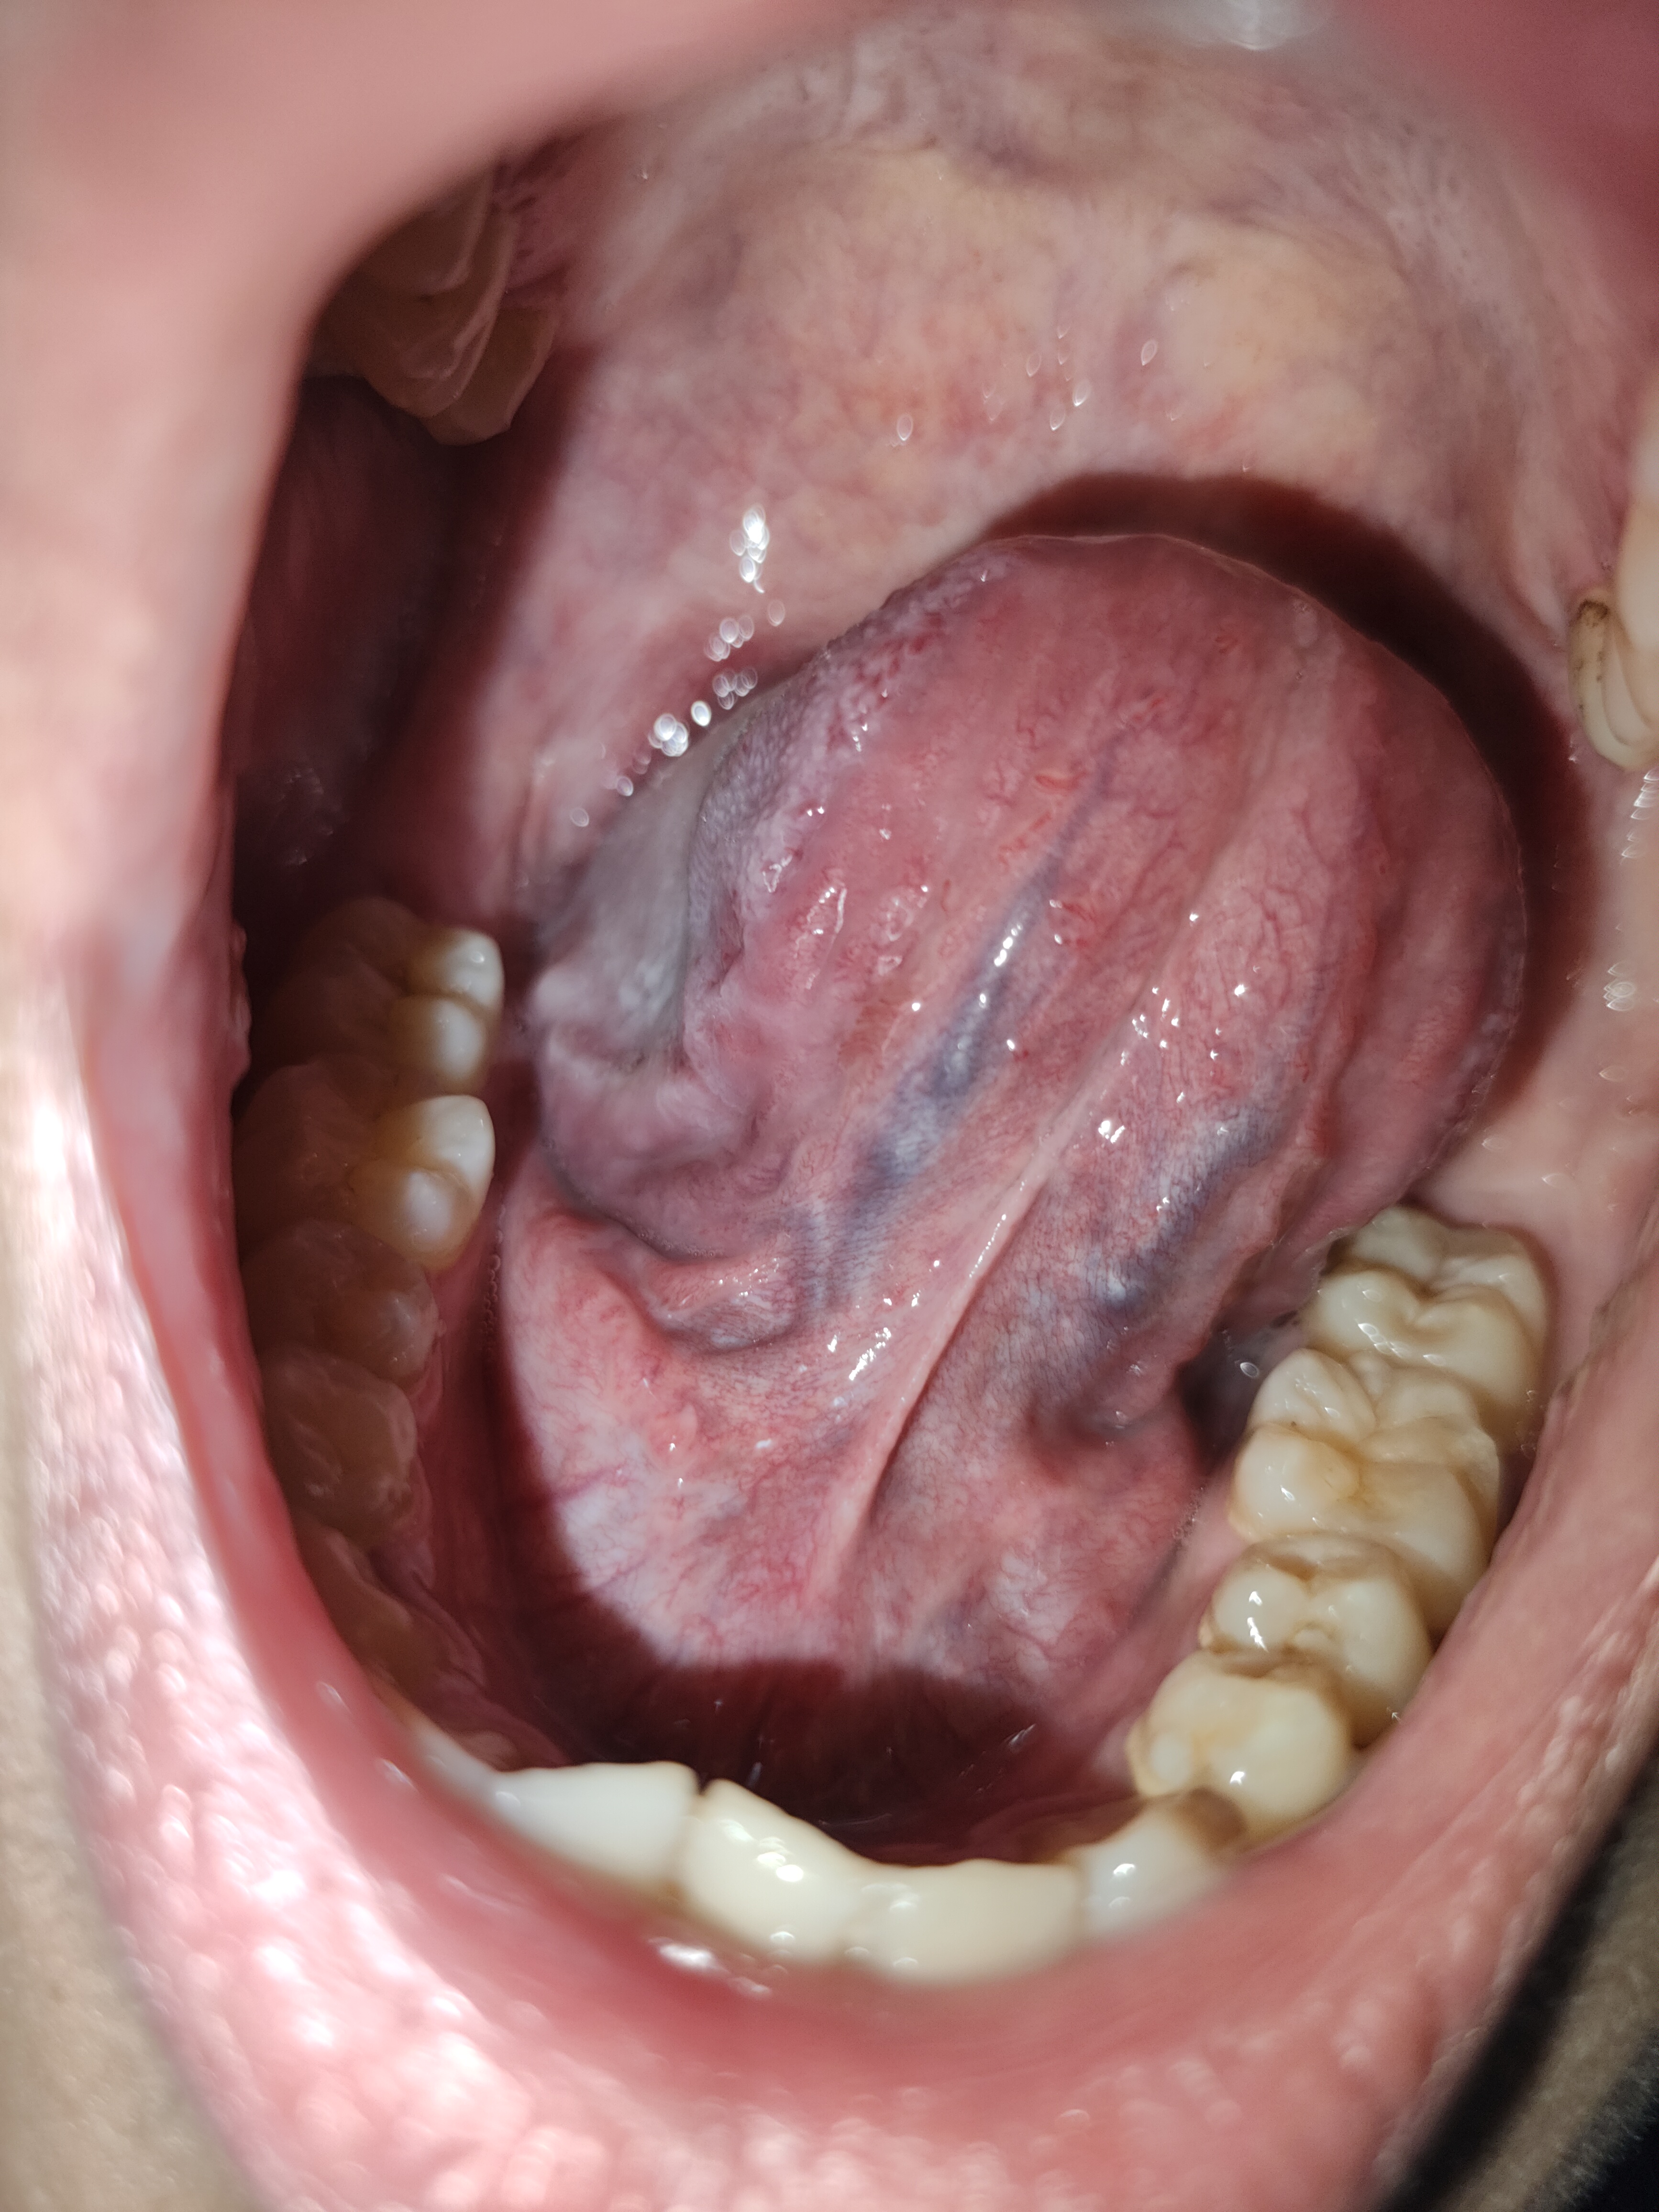

Bác sĩ ơi e có mọc mụn thịt ở phía dưới lưỡi không có giác gì cả . không biết là có nguy hiểm không bác sĩ tư vấn cho em với ạ

Bác sĩ không thấy bất thường ở đâu e ạ